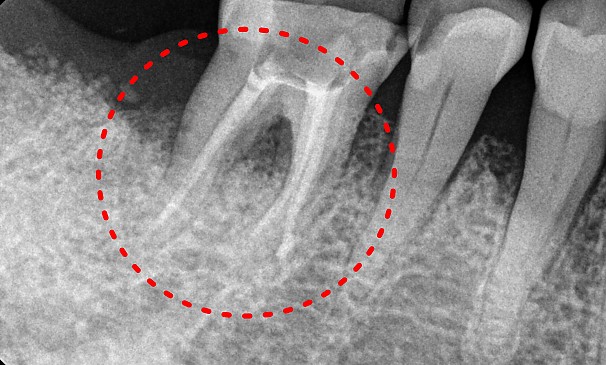

박OO님 전후사진 | 치료 기간 : 2주

치료 전

치료 후